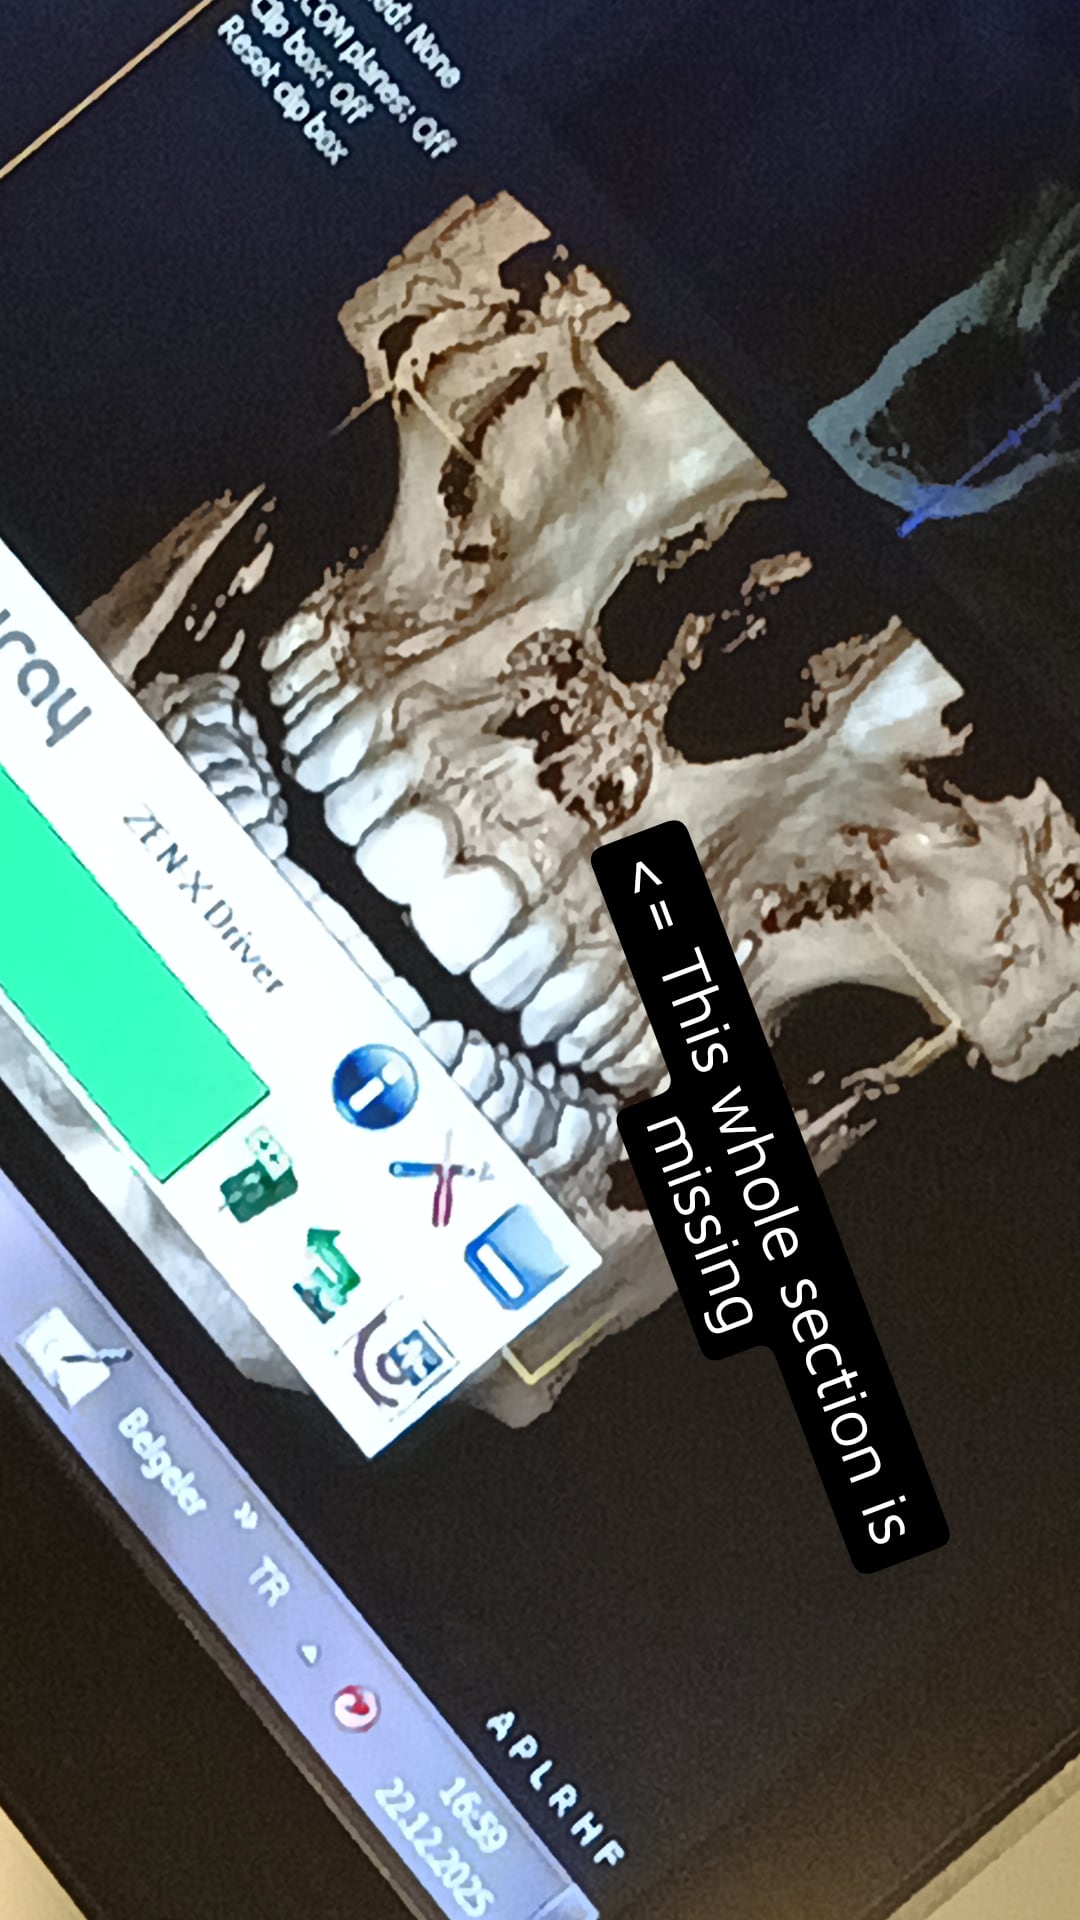

I was very slightly recessed and needed repair in my maxilla from a prior cyst in turkey right now and mf surgeon decided not to use general anesthesia but there is 0 pain even without the painkillers he has given me

Mid op:

I was very slightly recessed and needed repair in my maxilla from a prior cyst in turkey right now and mf surgeon decided not to use general anesthesia but there is 0 pain even without the painkillers he has given me

Mid op: